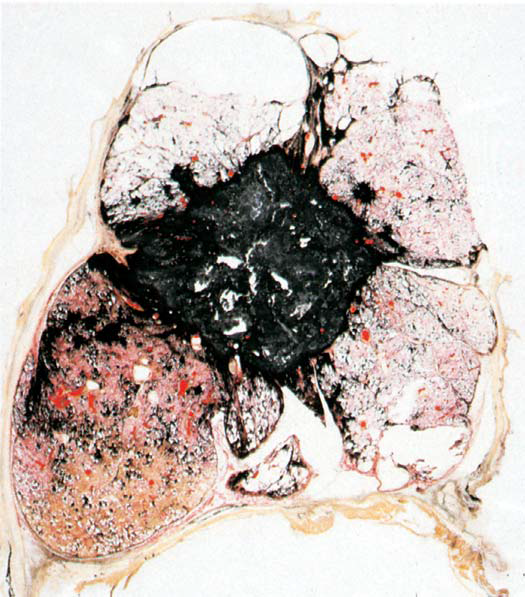

A coal miner presents to the clinic with pulmonary problems. The patient dies and his lung is shown at autopsy. The lung shows large bilateral upper zone fibrotic lesions with central cavitation. What is the likely Dx?

Progressive Massive Fibrosis